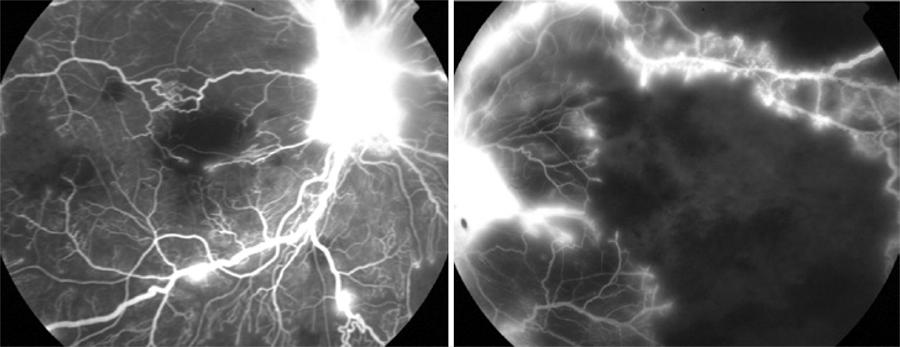

On ophthalmologic examination, a preferential looking test (Teller) showed visual acuity of 20/1000 in the right eye (OD) and 20/540 in the left eye (OS) at 38 cm. Direct pupillary reflexes and ocular motility were normal. Fundus examination showed bilateral retinal hemorrhages in the four retinal quadrants, cotton wool spots, macular edema and neovascularization in the optic nerve head (Figure 1). Fluorescein angiography showed hypofluorescent areas by blocking (hemorrhages) and filling defects (retinal ischemia), mild vascular tortuosity and late hyperfluorescence due to leakage around the optic nerve neovascularization in both eyes (Figures 2 and 3).

Figure 2 Fluorescein angiography demonstrating contrast leakage through the new vessels and nonperfused retinal areas.